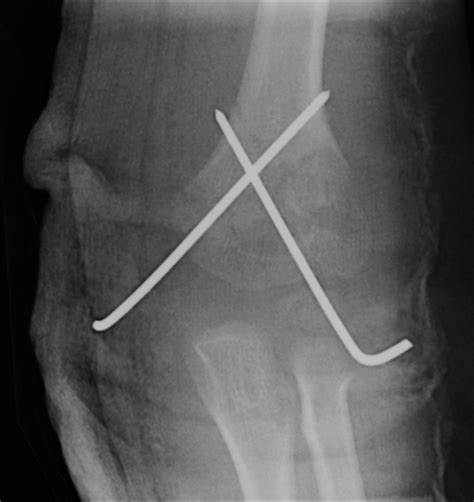

What is the management of supracondylar fractures?